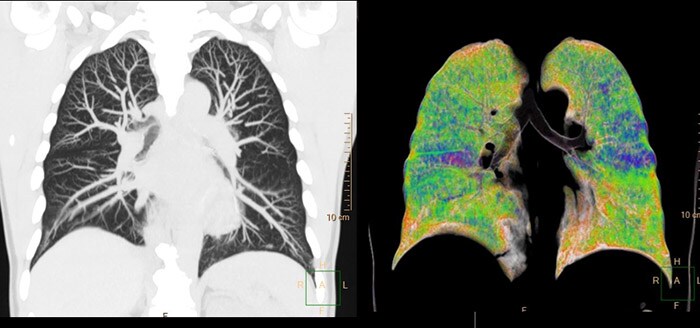

Philips will debut new technologies supporting its vendor-agnostic Radiology Workflow Suite at ECR, alongside its robust portfolio of clinically optimized diagnostic and interventional solutions. Philips Radiology Workflow Suite helps drive clinical and operational efficiency across all phases of the diagnostic enterprise, from scheduling and preparation, to image acquisition and data interpretation, to reporting and care pathway selection and treatment. New and enhanced solutions supporting Philips Radiology Workflow Suite include: Philips takes a holistic approach to integrating AI across its Precision Diagnosis portfolio, both for image processing and interpretation and for image acquisition, where automated and AI-enabled ‘smart workflows’ can increase efficiency and boost clinical confidence for system operators. Philips’ commitment to integrating data, AI, and analytics solutions supports its growing ecosystem approach, benefitting customers and the patients they serve. At ECR Philips is also showcasing innovations to enhance productivity and clinical confidence in diagnostic X-ray.